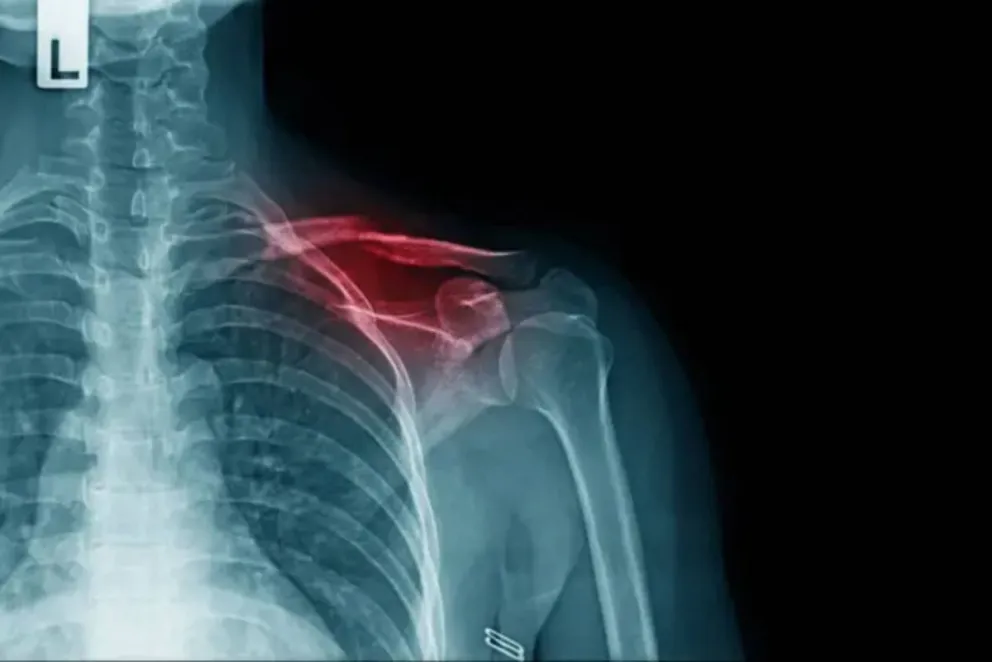

El hecho ocurrió el 8 de febrero, cuando Adela García sufrió una caída mientras circulaba en moto. Tras el accidente fue trasladada al Hospital Castro Rendón, donde recibió atención de urgencia y los médicos confirmaron que tenía una fractura de clavícula que requería intervención quirúrgica y la colocación de una prótesis.

La posibilidad de esperar tanto tiempo generó preocupación en la paciente. Según indicó, los médicos le advirtieron que las fracturas comienzan a consolidarse a las pocas semanas, lo que podría complicar una intervención tardía.

“Esperar dos meses con la clavícula quebrada era demasiado”, sostuvo. Mientras avanzaban los trámites, el hospital le informó que no podía proporcionarle la prótesis porque el sistema establecía que ese insumo debía ser cubierto por la obra social.